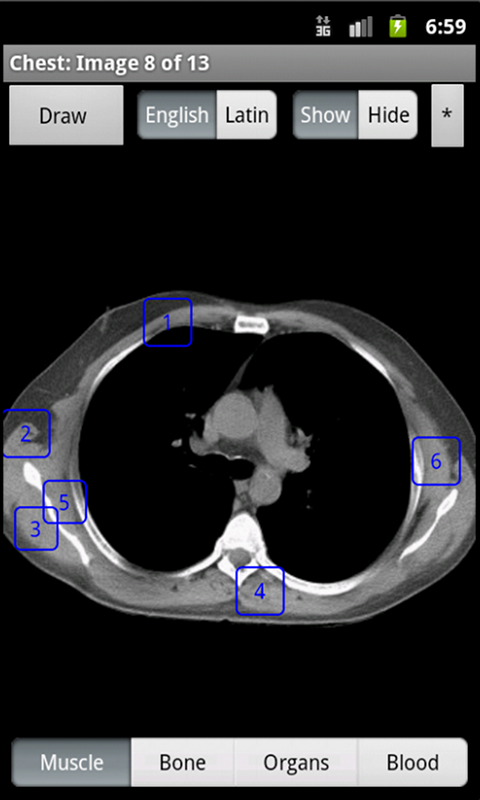

Learning anatomy interactively with a touchscreen device is dynamic and engaging. Having it as an app, makes the information available anywhere, anytime. Using the Samsung Pen, doctors can go over anatomy with patients, annotate normal anatomy images, and send the patient an email of the annotated image. This is a revolutionary way to increase doctor patient communication. iAnatomy is an exciting electronic anatomy atlas. The images are interactive. If a label is touched, the name of the structure is shown. Images span from the face to the pelvis. The face and neck images and the female pelvis images are reconstructed from data from the National Library of Medicine's Visible Human ProjectⓇ. iAnatomy is designed to stand on its own and does not require an ongoing internet connection. Anatomy labels can be hidden or shown. Anatomy can be viewed with either English or Latin medical terminology. A 'Draw' option allows the user to take an image, annotate it and mark it up and then save and/or email the annotated image. This is useful for healthcare workers using the image annotation to explain relevant anatomy and pathology to their patients. They can then email the image with their notations to the patient. This will help improve communication between patients and healthcare workers and is a useful tool for patient education.

iAnatomy helps students from middle school through medical school learn anatomy in a fun, organized way. You first choose the body part you want to study, then pick the category of anatomy labels to be displayed. The labels are divided into Muscle, Bone, Organs, or Blood categories in order to focus learning and limit the number of labels on the image at any one time.